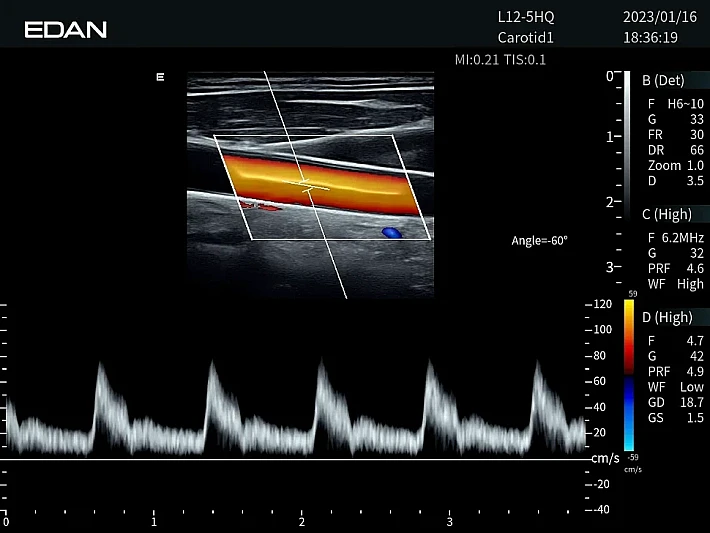

Медицинское оборудование и сервисное обслуживание